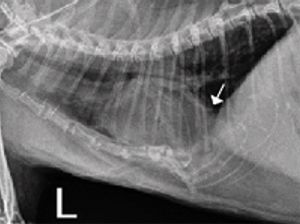

An approximately 1-year-old male Maltese dog was presented to the Veterinary Clinic of East Hampton for a routine castration.

This condition often goes unnoticed for years, and many cases are discovered incidentally on radiographs.

The outcome in this dog was not good, illustrating the necessity of identifying this disorder early.